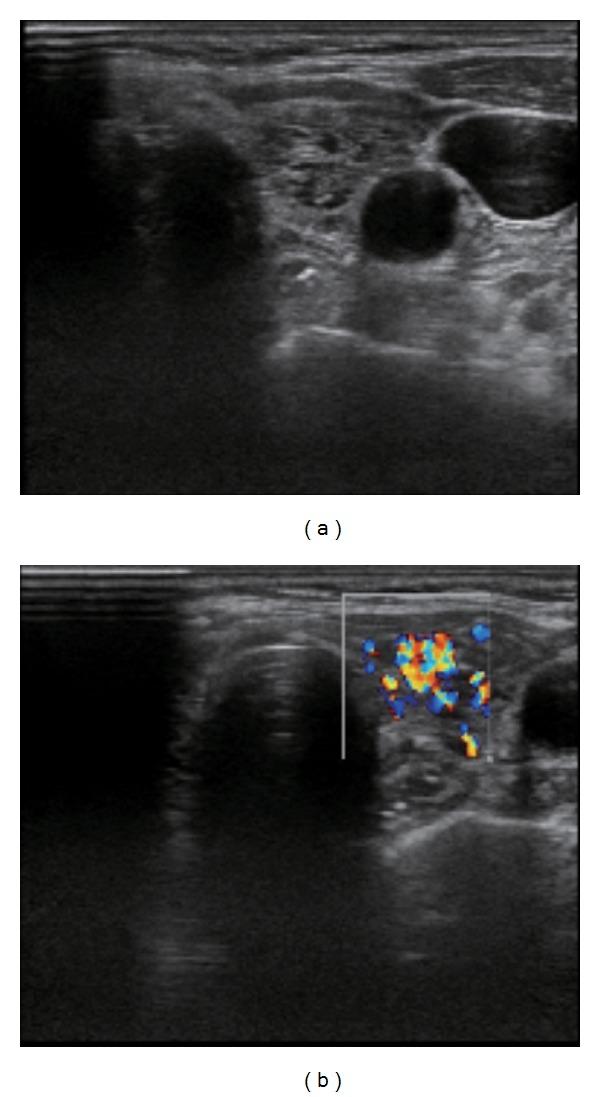

We herein describe a case of Marine-Lenhart syndrome with a negative TSH receptor antibody titer. A 75-year-old female presented to our hospital with malaise, palpitations, and mild fine tremors. She did not have any signs suggestive of Graves' ophthalmopathy, including conjunctival injection, periorbital edema, or proptosis. Her laboratory data were negative for thyroid autoantibodies, including anti-thyroid peroxidase antibodies, anti-thyroglobulin antibodies, and anti-TSH receptor antibodies (TRAb). Ultrasonography of the thyroid gland revealed a tumor in the right lobe. The remaining thyroid gland had an inhomogeneous and rough texture with a high color Doppler flow. I(123) scintigraphy disclosed a hot nodule in the right thyroid gland corresponding to the tumor detected on ultrasonography, suggesting Plummer disease. Furthermore, there was an increased uptake of radionuclide in the rest of the thyroid gland, despite the suppressed level of TSH and negative titer of TRAb, suggesting underlying Graves' disease. The present findings suggested a diagnosis of Marine-Lenhart syndrome with a negative TRAb titer. Treatment with 10 mCi of radioiodine was highly effective in treating hyperthyroidism in this case. A negative TSH receptor antibody titer does not necessarily rule out the existence of Graves' disease in patients with Plummer disease.

我们在此描述一例促甲状腺激素受体抗体滴度为阴性的Marine-Lenhart综合征病例。一名75岁女性因全身不适、心悸和轻度细震颤前来我院就诊。她没有任何提示Graves眼病的体征,包括结膜充血、眶周水肿或眼球突出。她的实验室检查数据显示甲状腺自身抗体呈阴性,包括抗甲状腺过氧化物酶抗体、抗甲状腺球蛋白抗体和抗促甲状腺激素受体抗体(TRAb)。甲状腺超声检查发现右叶有一个肿瘤。其余甲状腺质地不均匀且粗糙,彩色多普勒血流信号丰富。碘-123闪烁扫描显示右甲状腺有一个热结节,与超声检查发现的肿瘤相对应,提示为Plummer病。此外,尽管促甲状腺激素水平被抑制且TRAb滴度为阴性,但甲状腺其余部分的放射性核素摄取增加,提示存在潜在的Graves病。目前的检查结果提示诊断为TRAb滴度为阴性的Marine-Lenhart综合征。在该病例中,10毫居里放射性碘治疗对治疗甲亢非常有效。促甲状腺激素受体抗体滴度为阴性并不一定排除Plummer病患者存在Graves病。